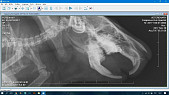

Вот рентгены недельной давности до подрезки зубов

Так же на нижней челюсти видно формирование как минимум двух периапикальных абсцессов. Требуется как минимум еще снимок в прямой проекции (вентро-дорсальной), чтобы посмотреть носовые ходы, раз есть хрипы, и определить степень перекоса челюстей, а так же посмотреть расположение корней верхних моляров, возможно, есть прорастание зубов в носовую полость.

Хорошо бы еще сделать снимок брюшной полости хотя бы в боковой проекции, посмотреть, нет ли газообразования в кишечнике или желудке. От этого будет зависеть назначение дополнительных препаратов в связи с жидким стулом. Возможно, потребуются антибиотики, стимуляторы перистальтики либо спазмолитики, а так же пробиотики.

На рентгене тимпания желудка, и содержимое в нем вызывает подозрение на волосяной ком (трихобезоар), хотя возможно это просто кормовые массы. Последите пожалуйста за регулярностью стула, при его задержке - сделайте рентген с контрастом (интервал дачи бария - 15 минут и 3 часа).

Ветеринар сказала, что абсцессов не видит, но завтра пощупает и если это не лимфатические узлы, то сказала если абсцессы маленькие - удалит без наркоза. Скажите пожалуйста, так правильно и видите ли вы абсцессы на новых снимках? Газового наркоза нигде нет. Спасибо за ответы!

Посмотрите пожалуйста есть ли на новых рентгеновских снимках абсцессы и где они точно находятся.

Прикладываем рентгены, спасибо!